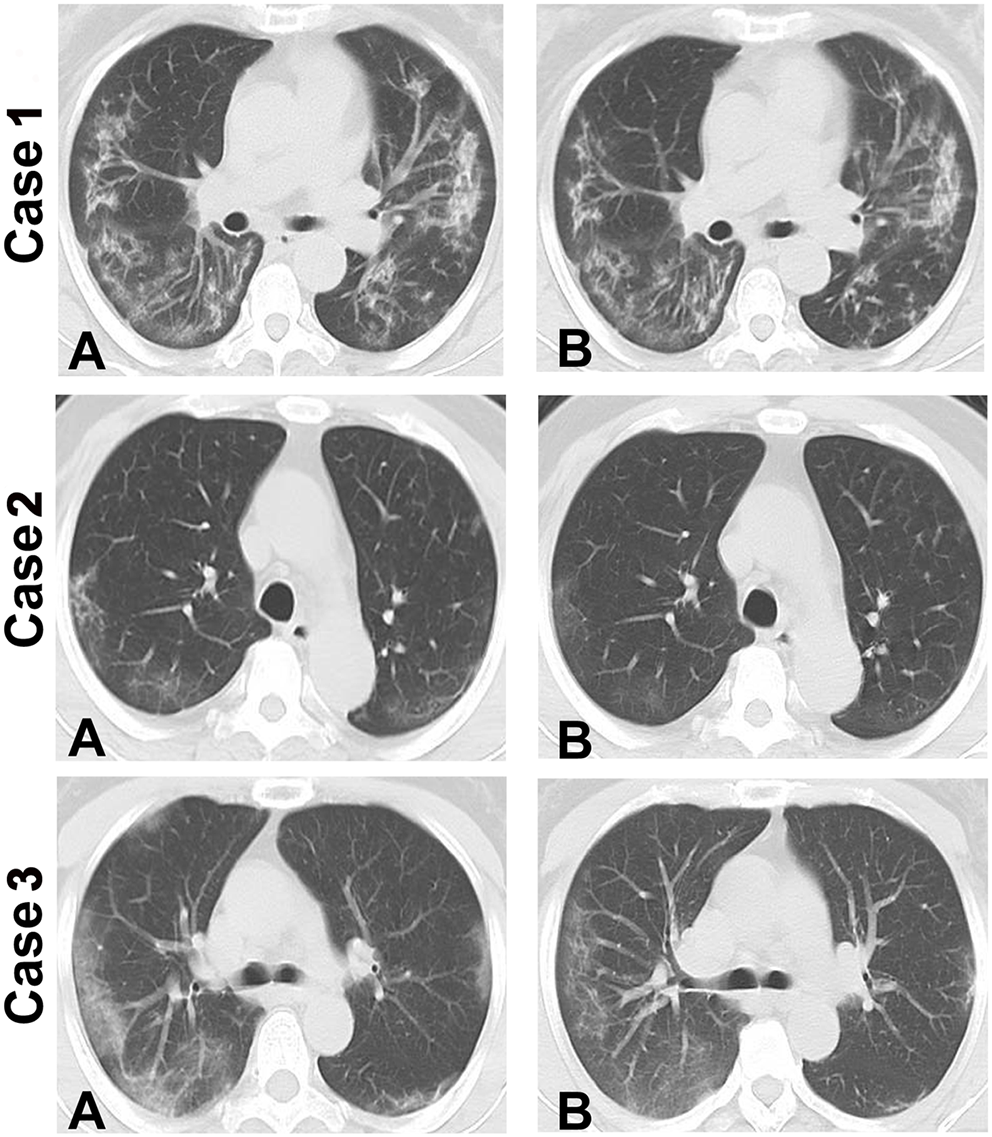

The criteria for ICU discharge includes absence of fever for 3 days or more, significant improvement in respiratory symptoms, chest CT showing significant absorption of exudative lesions (Figure 1), negative results from 2 consecutive tests for respiratory pathogen nucleic acid (at least 1 day between tests), and absence of a life-threatening major organ impairment. After meeting the criteria, patients can be transferred to the corresponding department for treatment.

Figure 1. Chest CT showing changes in 3 patients with severe COVID-19. Compared to the first transferred to ICU, chest CT showing significant absorption of exudative lesions in patient of the day before they were discharged from the ICU. (A) Chest CT images of the patients when they were first transferred to ICU. (B) Chest CT images of the patients on the day before they were discharged from the ICU showing absorption of the exudative lesions. Intensive care unit: ICU.